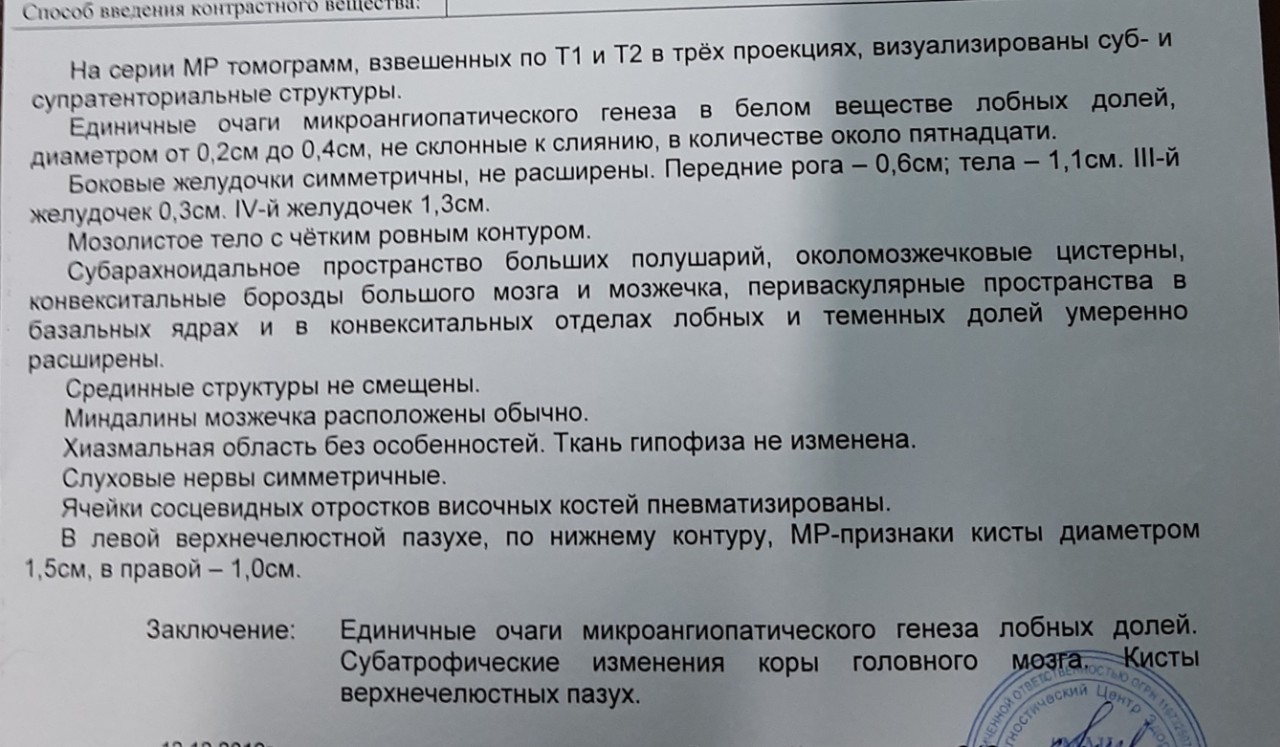

МРТ головного мозга: Расшифровка снимков и Интерпретация

Раздел: Визуальные уроки